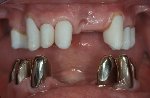

- Patient mit neuen keramischen Primärkronen im Oberkiefer

- © Dr. Paul Weigl

Der direkte Vergleich: Patient mit neuen keramischen Primärkronen im Oberkiefer und metallischen Primärkronen im Unterkiefer